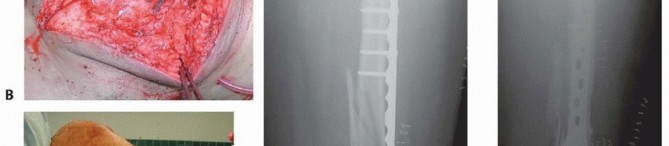

### TECH FIG 9 • A. Patient with significant metaphyseal bone loss from an open injury shown on CT scan. - B. The postfixation radiograph shows the void. C. Placement of OsteoSet beads impregnated with vancomycin (off-label use) to fill the void and provide osteoconductive material for healing. Multiple locking screws are used in the epiphysis because of the short length of these distal fragments. The largest screws available for the epiphysis should be used. ### Bone Grafting The metaphyseal comminution may require bone grafting or the use of bone substitutes in cases of open fractures with bone loss. The exact type and need vary and should be based on the surgeon's experience ( TECH FIG 9). In closed fractures, avoiding stripping of the medial soft tissues often allows for healing without bone grafting. 486 In open fractures with significant bone loss, we have had good success with the use of bone substitutes such as calcium sulfate (+/- antibiotics mixed in; off-label use), avoiding the need for later grafting (see FIG 11A-H). Hemostasis is achieved throughout the procedure or after the tourniquet is released. A tourniquet can be used to help minimize bleeding and improve visualization, especially for articular reconstruction. Often, a sterile tourniquet is used because of the temporary bridging external fixator that is in place. After adequate irrigation (before bone graft or substitute placement if used), a drain is placed in the knee joint and brought out laterally.

### TECH FIG 10 • A. Closure of the arthrotomy. B,C. Full flexion and extension of the knee after definitive fixation and closure. As seen in final AP (D) and lateral (E) radiographs, the metaphyseal comminution is bridged and left undisturbed. - Standard Wound Closure Closure of the arthrotomy is performed with figure-8 0 Vicryl sutures. This is reinforced by a running 2-0 FiberWire (Arthrex, Inc., Naples, FL) or Ethibond suture ( TECH FIG 10A). The subcutaneous tissue is closed with 2-0 Vicryl. The skin is closed with staples, as are the percutaneous stab incisions. The knee is flexed and extended fully to ensure restoration of motion as well as to break any adhesions in the quadriceps that may have formed while the temporary bridging external fixator had been in place ( TECH FIG 10B,C). The final radiographs are taken in the operating room ( TECH FIG 10D,E). 1. ## Open Reduction and Internal Fixation of the Distal Femur with Locking Plates (Type A or Nondisplaced Type C1 or C2) This technique can be used regardless of the locking plate system used. Each system's technique guide should be reviewed before use as each system has its own idiosyncrasies. Variations in plate application as well as reduction tools and techniques are unique to each system. See comments earlier regarding temporary use of an external fixator or distractor. ### Limited Lateral Approach A lateral incision measuring about 5 to 6 cm is made starting at the level of the joint and extending proximally in line with the shaft. The distal extent is curved slightly toward the tibial tubercle, as in the lateral approach ( TECH FIG 11A,B). The iliotibial band is incised in line with the skin incision ( TECH FIG 11C). The dissection is carried down to the lateral femoral condyle. The lateral aspect is exposed enough for plate placement ( TECH FIG 11D). A Cobb elevator is used to create a plane submuscularly up the lateral shaft of the femur for placement of the plate.